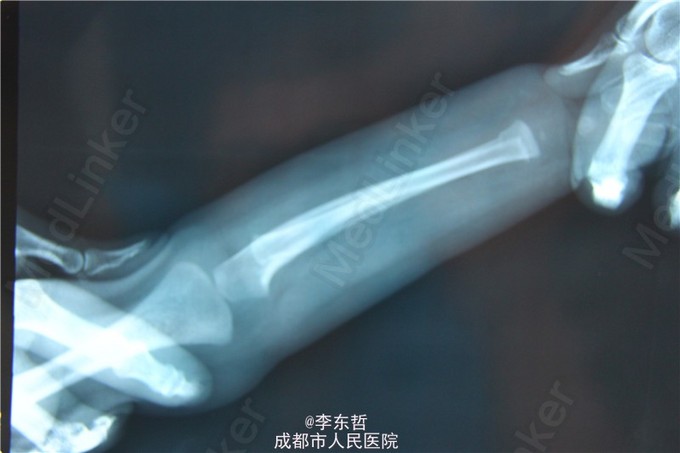

小儿左桡骨远端青枝骨折

患儿1岁, 在练习走路过程中不慎摔倒, 左手撑地. 回家发现爬行困难, 左手不敢着地. 来院拍X光后, 确定为左桡骨青枝骨折.